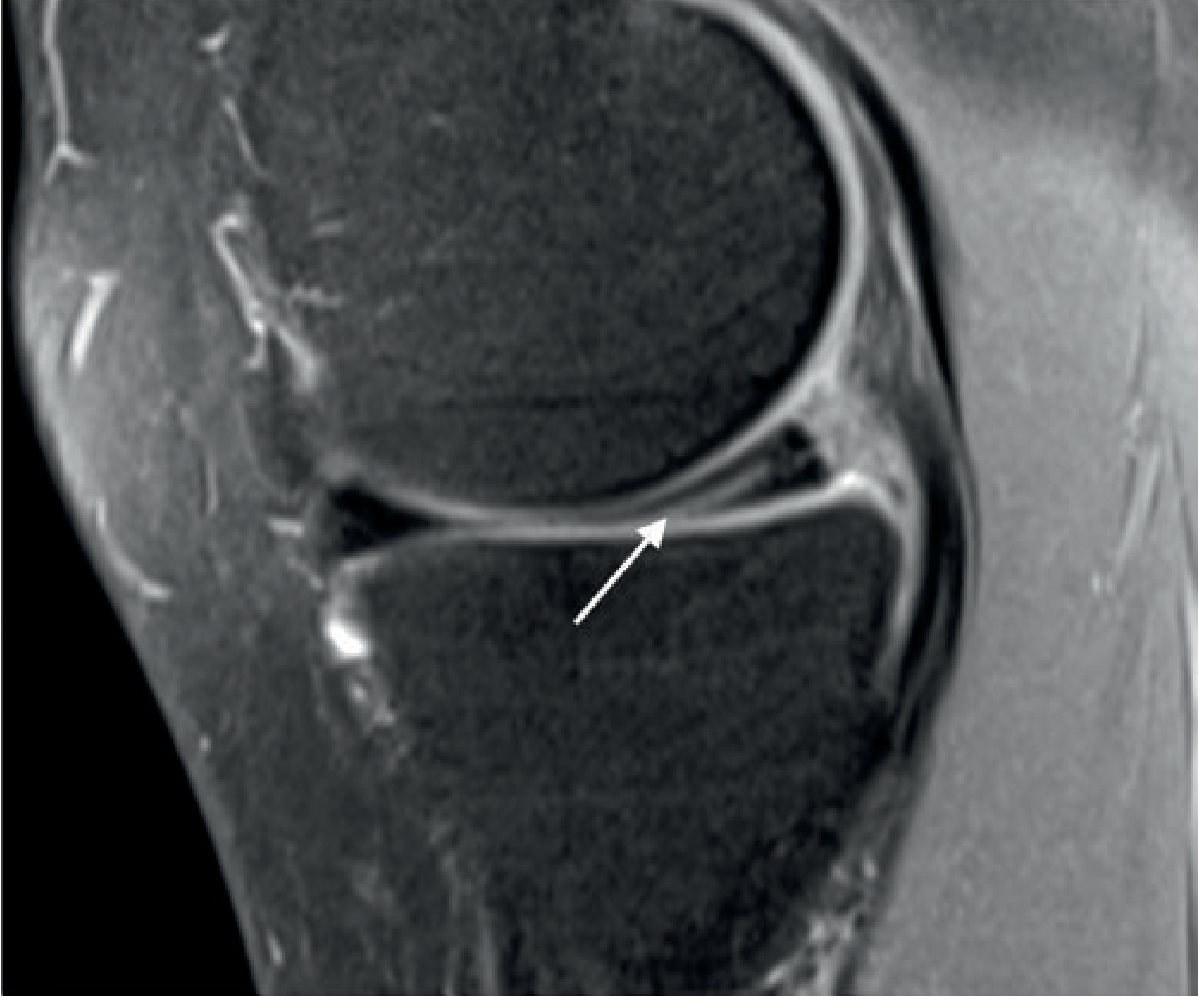

Sagittal PD fat-saturated MRI — horizontal undersurface tear of the posterior horn of the medial meniscus (arrow)

Horizontal tear — posterior horn medial meniscus (Grainger & Allison's Diagnostic Radiology)